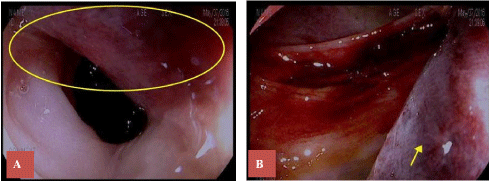

Colorectal surgery was consulted, and a bedside flexible sigmoidoscopy performed. A sub-mucosal hematoma was found on a 10-cm segment of the sigmoid approximately 25-35 cm from the anal verge. No intraluminal bleeding was seen, but a fresh adherent clot was identified in the suspected fistula region (Figure 3A and Figure 3B).

Figure 3: A) Area of suspected fistula encircled; B) Sub-mucosal hematoma between 25-35 cm from anal verge (arrow). View Figure 3